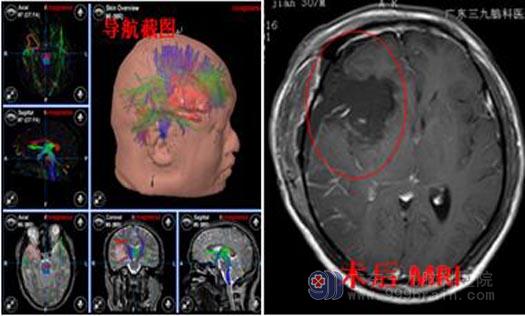

转入广东三九脑科医院行头颅核磁共振检查,提示:右侧额颞岛叶外囊区占位性病变,范围约63mm×77mm×54mm,考虑为弥漫性星形细胞瘤可能性大。完善相关检查后,由鲁明主任主刀行“唤醒麻醉下右侧额颞岛叶占位病变切除术”。显微镜下见肿瘤呈胶冻状,血供丰富,分块次全切除,术腔严格止血,过程顺利,术后病理:肥胖型星形细胞瘤,IDH突变型,WHO II级。